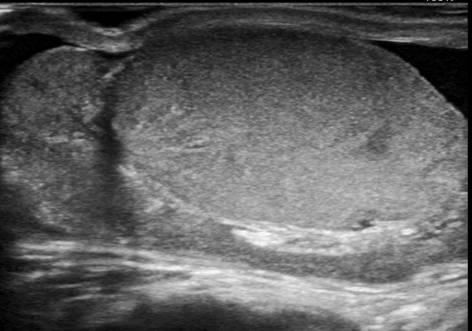

Viêm tinh hoàn - mào tinh

Viêm tinh hoàn – mào tinh

» Thông tin: Nam giới – 34 tuổi.

» Lâm sàng: Sưng đau vùng bìu.

# Tăng kích thước và tín hiệu mạch trên doppler tinh hoàn và mào tinh hoàn.